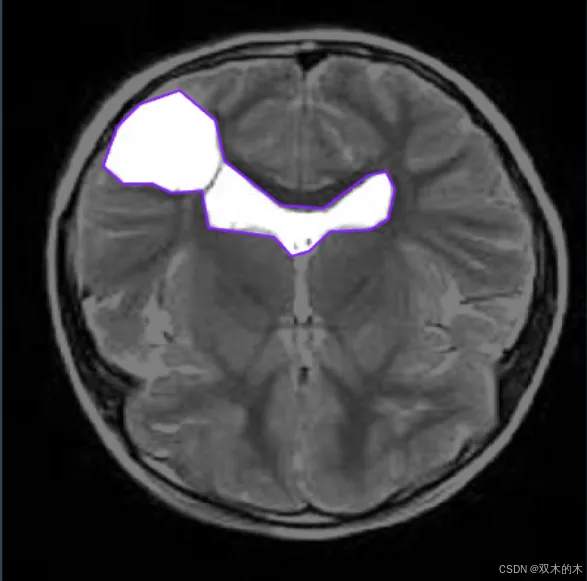

数据收集:收集表示要检测的类的图像。在此示例中,我们将使用 BRAIN-TUMOR 数据集,其中包含来自 roboflow 的 834 张图像。

链接 :https://universe.roboflow.com/iotseecs/brain-tumor-yzzav